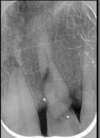

4- les implants en remplacement de dents infectées

Les dents portant un bridge ancien se sont infectées

Après extraction, deux implants et une prothèse provisoire implanto portée sont installés

Après une phase de cicatrisation de 4 mois, le bridge définitif peut-être réalisé